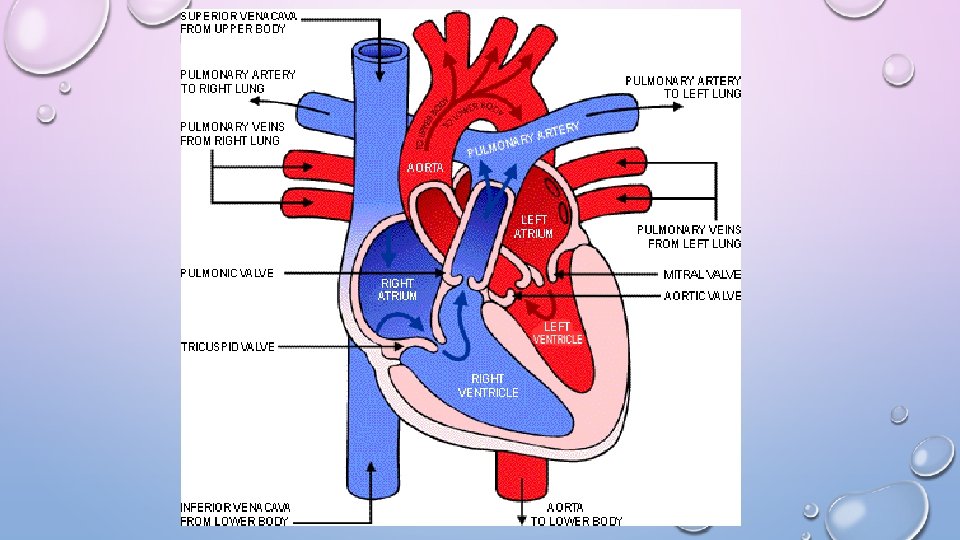

• PULMONARY CIRCUIT- BLOOD FLOW BETWEEN RIGHT SIDE OF THE HEART TO LUNGS AND LEFT SIDE OF HEART • “LUNGS LAP” • SYSTEMIC CIRCUIT- PATHWAY BETWEEN RIGHT AND LEFT SIDES OF THE HEART • “BODY LAP”

THE HEART • CARDIAC MUSCLE WITH INTERCONNECTING CELLS • (INTERCALATED DISCS) • 4 CHAMBERS: • 2 ATRIA (LEFT AND RIGHT) • AURICLES (LOOK LIKE EARS/FLAPS) • 2 VENTRICLES (LEFT AND RIGHT)

THE HEART • MAJOR VEINS • SUPERIOR VENA CAVA AND PULMONARY VEINS • MAJOR ARTERIES • AORTA AND PULMONARY TRUNK

PATHWAY OF BLOOD 6. LUNG 1. SUPERIOR OR INFERIOR VENA CAVA 7. PULMONARY VEIN 2. RIGHT ATRIUM 8. BICUSPID VALVE 3. TRICUSPID VALVE 9. LEFT VENTRICLE 4. RIGHT VENTRICLE 10. AORTIC SEMILUNAR VALVE 5. PULMONARY SEMILUNAR VALVE 11. AORTA 12. BODY